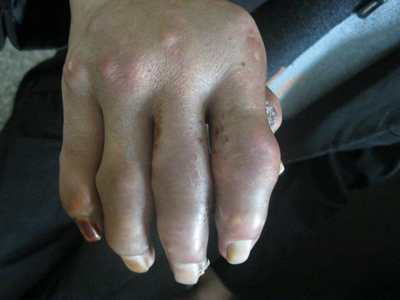

痛风急性发作时,表现为关节红肿、灼痛、感觉过敏、活动受限,伴畏寒、发热、头痛、乏力和纳差等症状。常于夜间发作,白天缓解,入夜又发,经几日到几周发作而逐渐停止,关节疼痛缓解。

痛风病程较长,常反复发作而迁延不愈形成痛风石,是痛风的特征性临床表现,常见于指关节、第一跖趾关节、耳廓等处。外观为隆起、大小不一的不规则的黄白色赘生物,表面菲薄,破溃后排出白色粉状或糊状尿酸盐结晶物,经久不愈,但较少继发感染。部分患者伴有肾结石及肾脏病变。